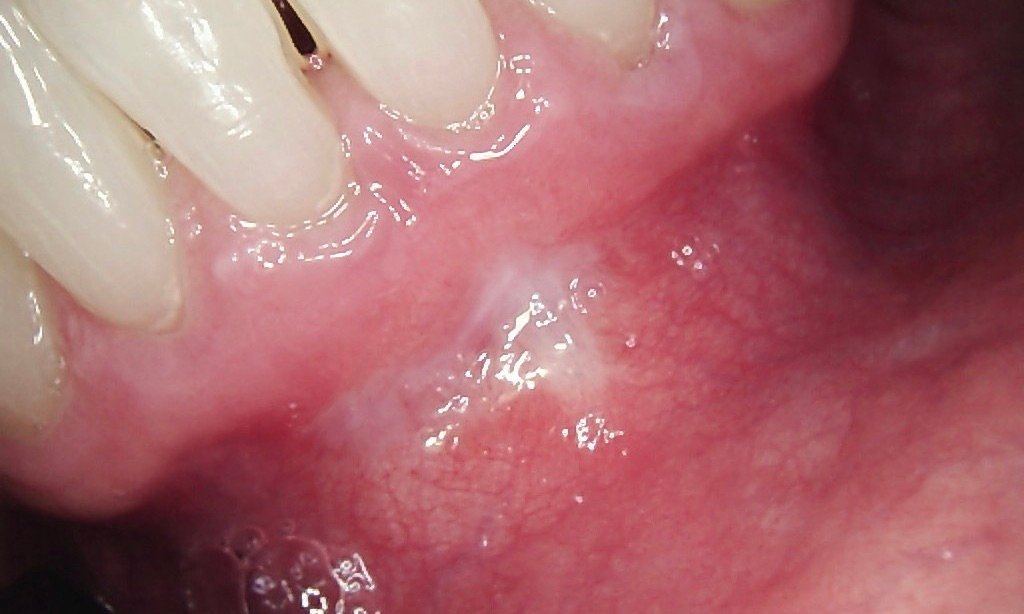

Fixing a “Gummy” Smile: If your gums cover too much of your teeth, making them appear short or uneven.

Cosmetic Laser Gum Contouring: We reshape excess tissue to reveal more of your natural teeth, creating a balanced and symmetrical smile line.

Modern laser procedures are designed to create a perfect frame for your teeth. By removing excess tissue with precision, we give you a smile you’ll be proud to show off instantly.